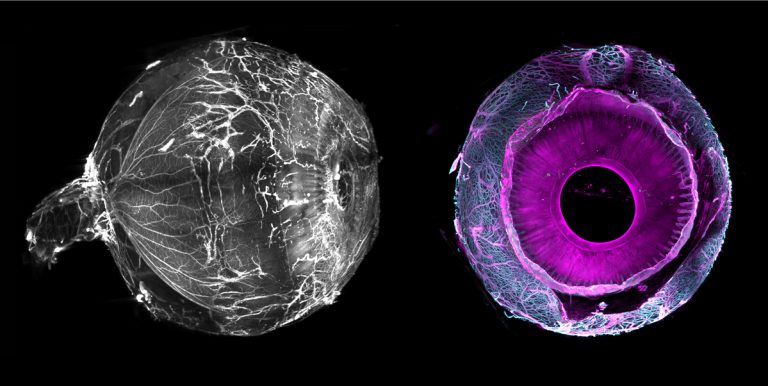

Un œil humain rendu complètement transparent